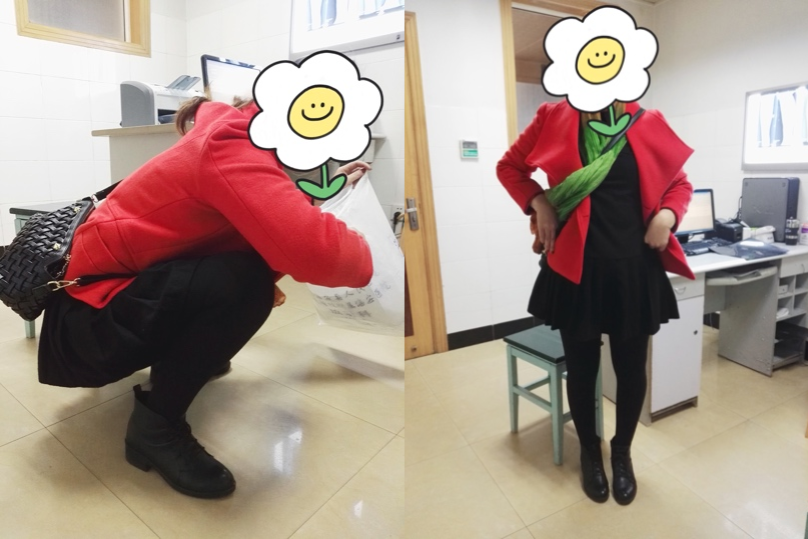

术后复查